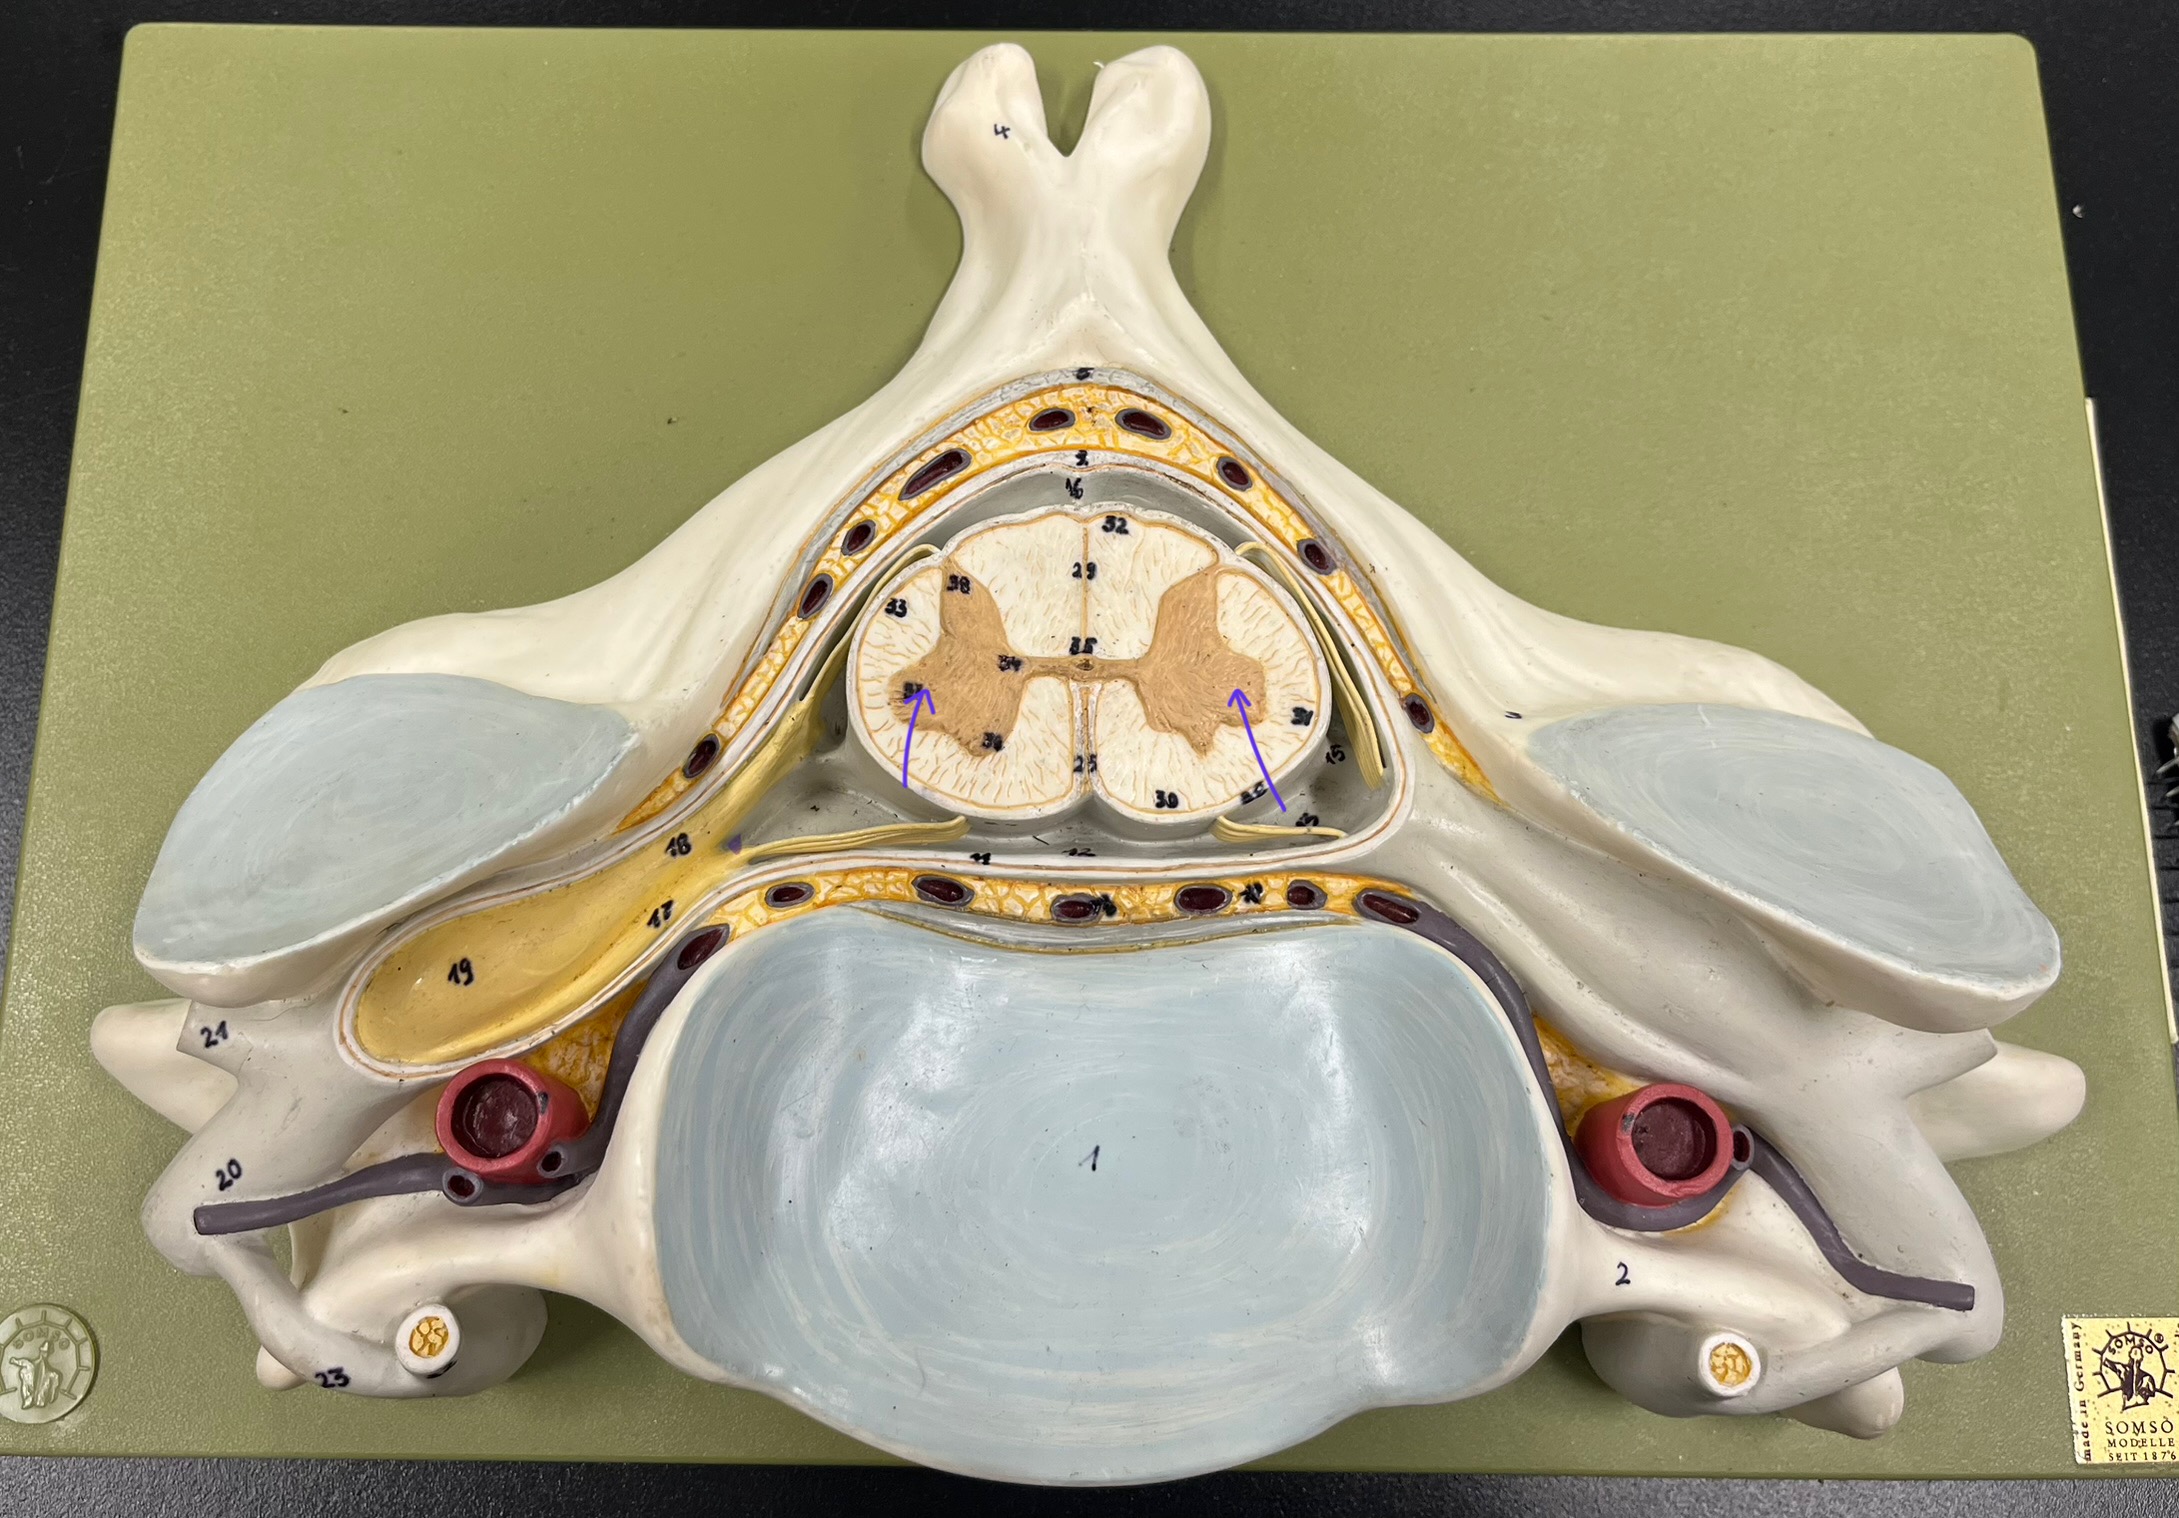

What is the groove here?

anterior median fissure

posterior median sulcus

posterior (dorsal) horn

posterior (dorsal) horn; R—>L

anterior (ventral) horn

lateral horn (selected models)

gray commissure

central canal

anterior column

lateral column

posterior column

white commissure

posterior (dorsal) root ganglion

What is the bulb here?

posterior (dorsal) root ganglion

posterior (dorsal) root

posterior (dorsal) root

anterior (ventral) root

anterior (ventral) root

dorsal ramus

dorsal ramus

ventral ramus

ventral ramus

rami communicantes

rami communicantes

sympathetic chain ganglia

sympathetic chain ganglia